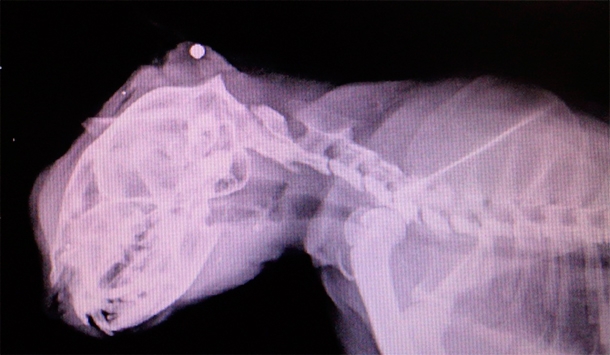

Несчастное и искалеченное животное обнаружили на улице случайные прохожие. Они незамедлительно принесли его в ветеринарную клинику. Врач после осмотра кота отправил его на рентген. Когда снимок был готов, выяснилось, что животному чудом удалось выжить, сообщается на странице ветеринарной клиники "Панацея" в социальной сети "ВКонтакте".

В затылочной части черепа застряла пуля из автоматической винтовки. Ветеринары тут же приняли решение во что бы то ни было спасти кота. Как позже рассказала врач, проводившая операцию, пулю сразу же извлекли, однако животному пришлось перенести не одно хирургическое вмешательство, а целых два. Ему также собрали два перелома нижней и верхней челюстей. Коту-герою дали кличку Киря. Пока он до сих пор живет в клинике, однако волонтеры очень надеются, что в скором времени животное реабилитируется и найдет себе новых хозяев.